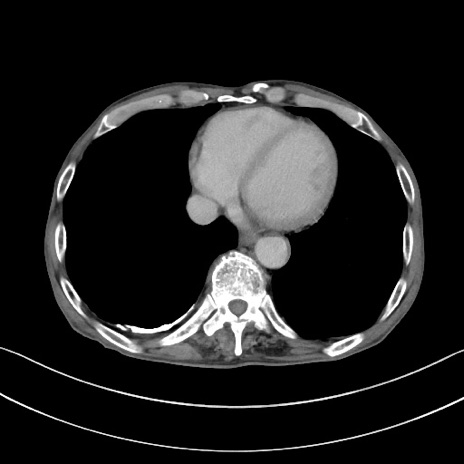

冠状断像

【症例】 70歳代男性

【主訴】右鼠径部腫瘤、疼痛

【現病歴】本日朝より上記主訴あり、受診。

【既往歴】膀胱癌にて膀胱全摘、両側尿管皮膚瘻

【データ】WBC 5600、CRP 0.56